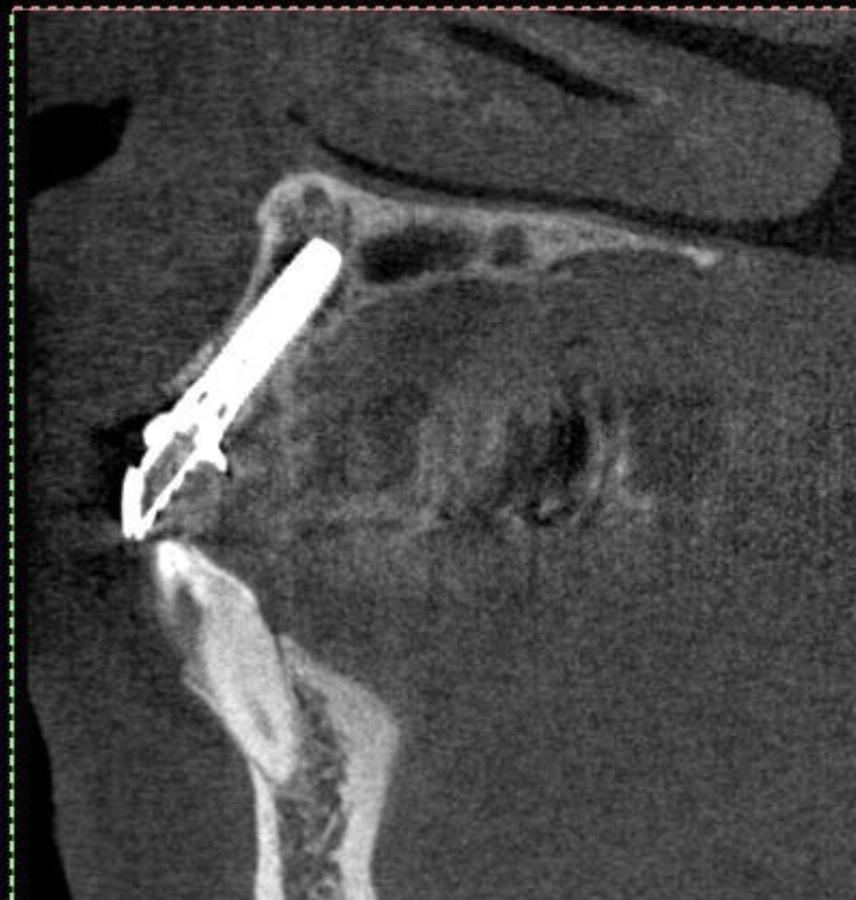

当日、抜歯とインプラントを同時に入れました。

4本抜歯して2本のインプラントを入れました。